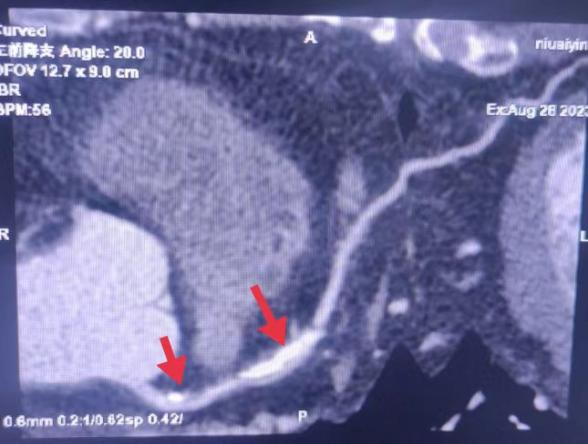

06、**男士,53岁

于2023年10月5日在邯郸仁泰南区体检,腹部彩超检查提示:右肾实质内见大小约3.0*2.4cm低回声,边界清,形态规整。诊断右肾低回声,建议客户到三甲医院进一步检查。首次回访:2023年10月10日电话回访,客户已在中心医院进一步检查, 明确病变的性质。2023年10月31日跟踪回访,客户已在中心医院完成手术治疗。